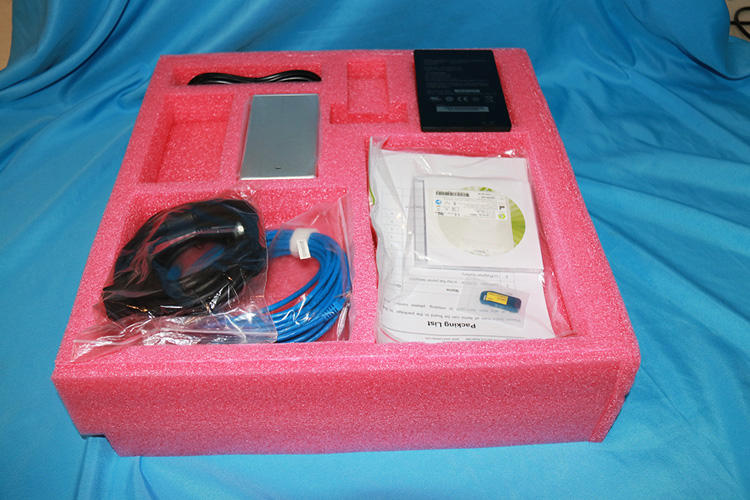

High Quality 17 x 17 Wireless Flat Panel Detector Price for Digital Radiography

- Medsinglong Co Ltd

| Effective area (mm): | 345.6*420 | brand: | MSL |

| Preview image: | 3 | Instrument classification: | secondary |

| Spatial Resolution (lp/mm): | 3.4 | product name: | Dr X-ray Flat Panel Detector |

| model: | MSLCV08 | AD conversion (bits): | 14 |

| place of origin; place of origin: | Guangdong, China | After-sale service: | Online technical support |

| payment terms: | L/C,Western Union,D/P,D/A,T/T,MoneyGram,Cash | Packaging Details: | standard packaging |

| Data Interface/Detector Control: | Wifi | Material: | Metal plastic |

| Quality Certification: | SG | Energy source: | Electricity |

| size of the picture: | 17*17 inches | port: | Guangzhou |

| Pixel count: | 2304*2800 | Warranty: | 2 years |

| safety standard: | EN 149-2001+A1-2009 | Supply capacity: | 10000000 sets per month |

| Shelf life: | 2 years | scintillator: | Csl/GOS |

| Detection Technology: | Amorphous silicon |

The MSLCV08 is a 17X17 box-type wireless portable flat panel detector designed for human digital radiography.

feature

- 1. Fast workflow

2. More image details

3. Excellent image quality

4. Cassette Flat Panel Detector